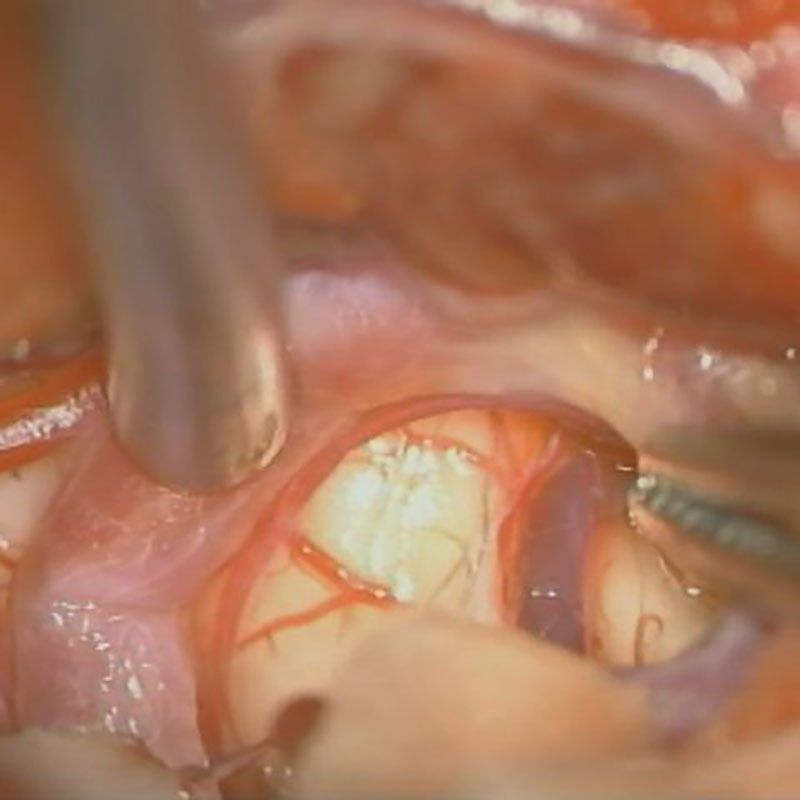

手術前

クリップ前

クリップ後

手術後